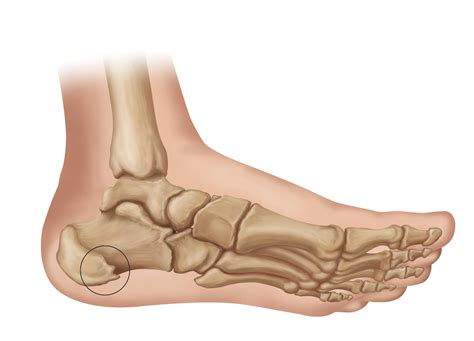

Bone spurs on feet, also known as osteophytes, are bony projections that develop along bone edges. These spurs can form on any bone but are particularly common in the feet, where they often develop in response to injury, wear and tear, or underlying conditions like arthritis. Understanding the causes, symptoms, and treatment options for bone spurs on feet is crucial for managing this condition effectively.

Bone spurs are essentially the body's response to stress or damage. When the body detects damage or stress, it attempts to repair the area by building extra bone. Over time, this extra bone can form a spur. In the feet, bone spurs often develop in areas that bear significant weight, such as the heels, toes, and the balls of the feet.

Diagnosing Bone Spurs on Feet

• Order imaging tests such as X-rays, CT scans, or MRIs to visualize the bone spur and determine its size and location.